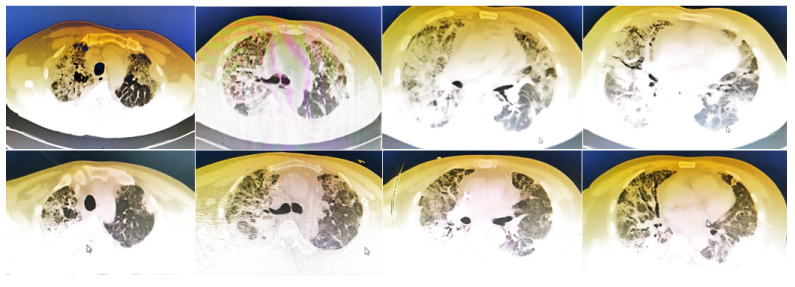

患者于2022年11月10日在全身麻醉下行左肺下叶部分切除+淋巴结活检术,手术过程顺利,入量1200 ml,尿量600 ml,出血10 ml。术后病理提示微浸润腺癌。术后顺利拔除气管插管,生命体征平稳。术后第3天开始出现活动后稍气喘,无明显发热,偶有咳嗽,咳白色黏痰。胸闷气喘症状逐渐加重。肝肾功能正常,D-二聚体正常,心肌标志物正常,未查血气和胸部CT;白细胞、CRP升高明显(表1)。予哌拉西林他唑巴坦+莫西沙星加强抗感染治疗。术后第5天胸部CT可见少量病灶(图2)。术后第12天胸部CT提示两肺间质性改变,右肺为著,局部可见支气管牵拉变形,磨玻璃影(图3)【普通感染不应出现如此变化,但当时并未引起重视】。后续患者出现呼吸衰竭,血气分析:pH 7.34,PaO2 53.1 mmHg,PaCO2 35.1 mmHg(面罩吸氧10 L/min)。转至ICU进一步治疗。

(1)感染性疾病:病毒性?细菌性?真菌?非典型病原体?吸入性肺炎?(2)非感染性疾病:心衰?急性肺栓塞?自身免疫性疾病?麻醉/手术相关肺损伤?急性间质性肺炎?回顾分析患者入院时胸部CT: 双肺靠近外周近胸膜处有轻微细小间质样改变(图4)。诊断:急性间质性肺炎;Ⅰ型呼吸衰竭;左肺下叶部分切除术后;高血压病。ECMO支持;呼吸机支持;甲泼尼松80 mg q12h,尼达尼布;镇静镇痛;抗感染;营养支持。ECMO第6天, 术后第18天, 肺部病变进一步加重(图5)。血气分析: pH 7.543, PaO2 154 mmHg, PaCO2 33.2 mmHg(ECMO, FiO2 100%, MV FiO2 60%)。术后第26天复查胸部CT未见改善。患者最终死亡。笔者团队也曾接诊过一例早期肺癌患者,2013年和2014年随访肺部结节均无明显变化。2015年胸部手术后2天,两肺变白(图6)。当时医生警惕性非常高,立刻行胸部CT检查并予相应治疗,患者最终存活。2022年RadioGraphics 杂志报道一例85岁女性腺癌患者奥希替尼治疗5个月后。图7-A和B为治疗前胸部CT图像,可见右肺中叶有肿块(A中箭头)。胸膜下区域磨玻璃改变和网状结构(箭头)提示存在间质性肺异常(Interstitial Lung Abnormalities,ILA)。治疗5个月后的轴位CT图像显示肿块(C中白色箭头)、弥漫性磨玻璃改变和合并症(黑色箭头)。图源:Radiographics, 2022, 42(7):1925-1939.另一例66岁右上肺鳞癌患者,术前CT显示肿块(图8-A中箭头)位于肺右上叶。轻度磨玻璃改变(箭头),提示ILA,见于胸膜下区域。图8-C和D为术后CT,显示弥漫性磨玻璃样改变和实变(箭头),牵引性支气管扩张症(图8-C中箭头),也可见胸腔积液(图8-D中箭头)。图源:Radiographics, 2022, 42(7):1925-1939.